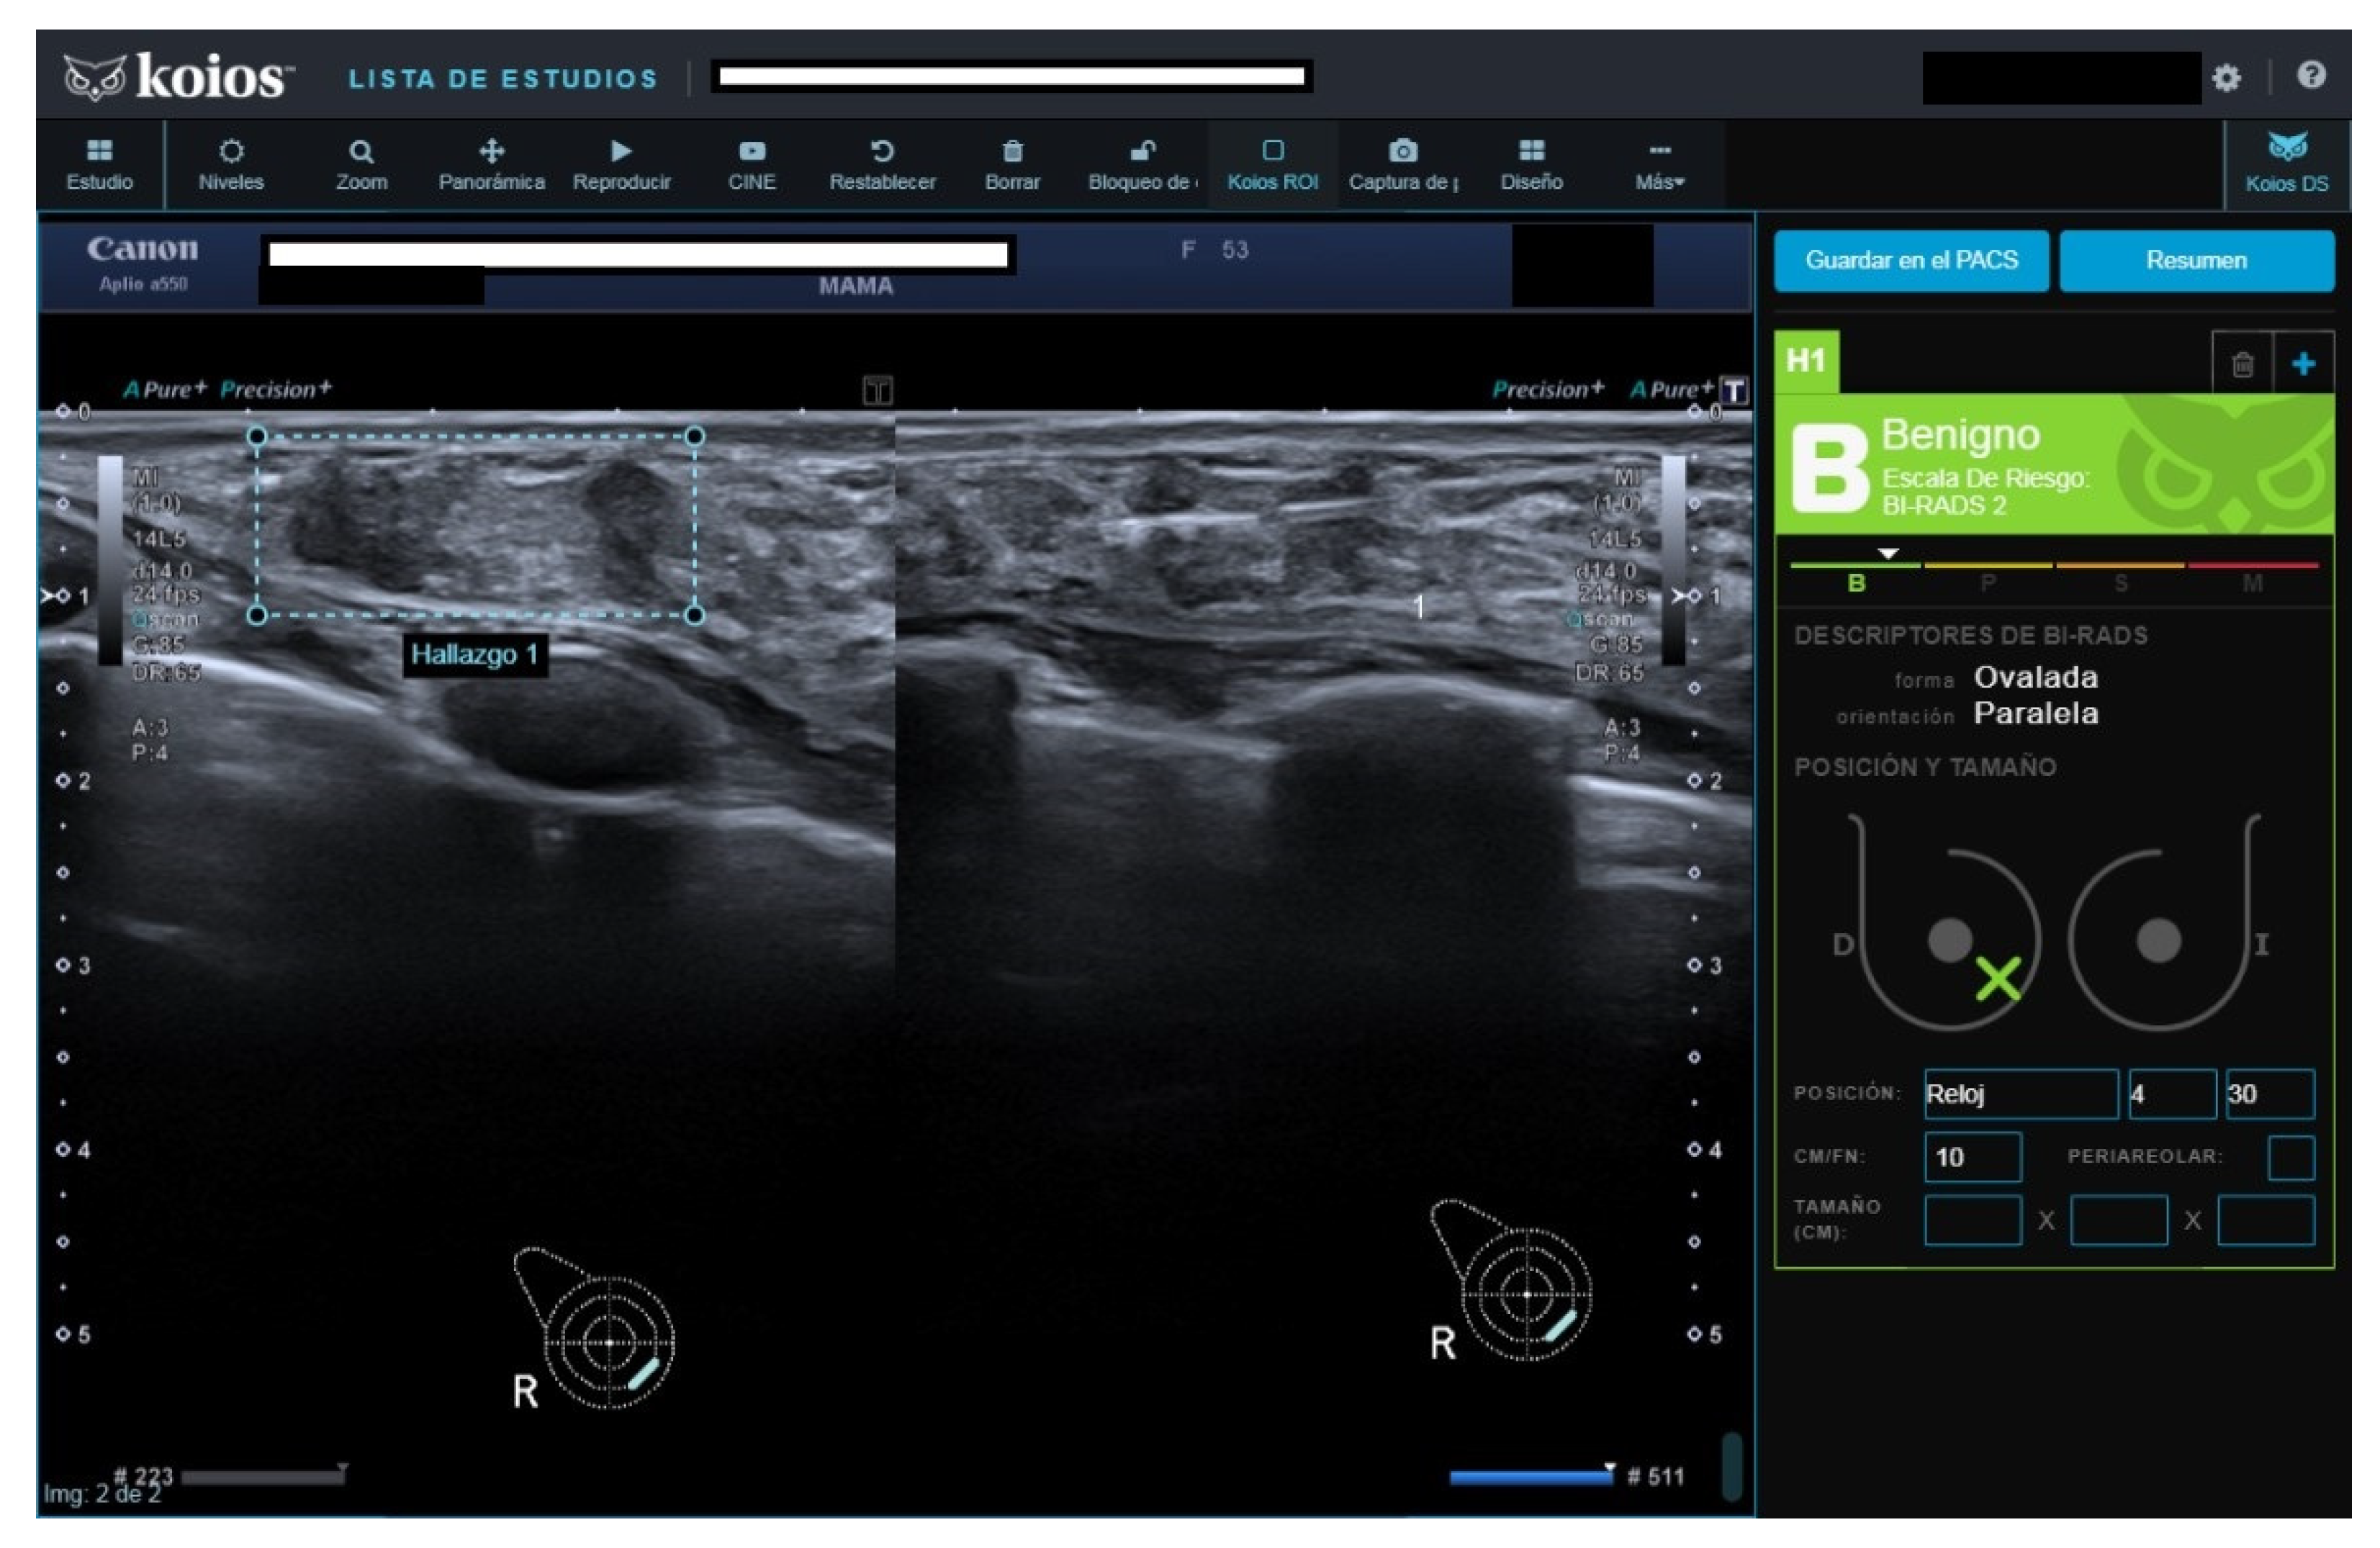

Figure 5.

New nodule in right breast with previous carcinoma 25 years before. Rated B4a, Kbe by KOIOS. Surgery rendered a malignant fibrous histiocytoma.